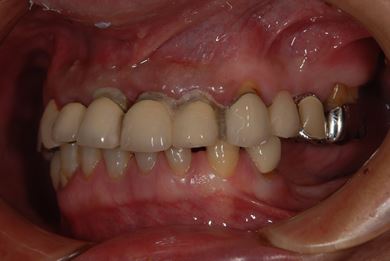

インプラントの症例写真 IMPLANT

骨再生スピードインプラント治療+セラミック治療

| 性別/年齢 | 男性 / 53歳 | ||||||||||||||||||||||||||||||||

| 主訴 | インプラント治療の相談。 | ||||||||||||||||||||||||||||||||

| 治療方針 | 上前歯部は、抜歯と同時にインプラントを埋入し、治療期間を短縮する。左上奥は、ソケットリフトにて上顎洞を拳上し、インプラント治療を可能にする。 | ||||||||||||||||||||||||||||||||

| 治療内容 | インプラント4本(ソケットリフト・抜歯即日)、テンポラリーインプラント2本、メタルボンドクラウン9本 | ||||||||||||||||||||||||||||||||

| 総治療費 | 2,025,975円 | ||||||||||||||||||||||||||||||||

| 治療期間 | 1年9ヶ月 |